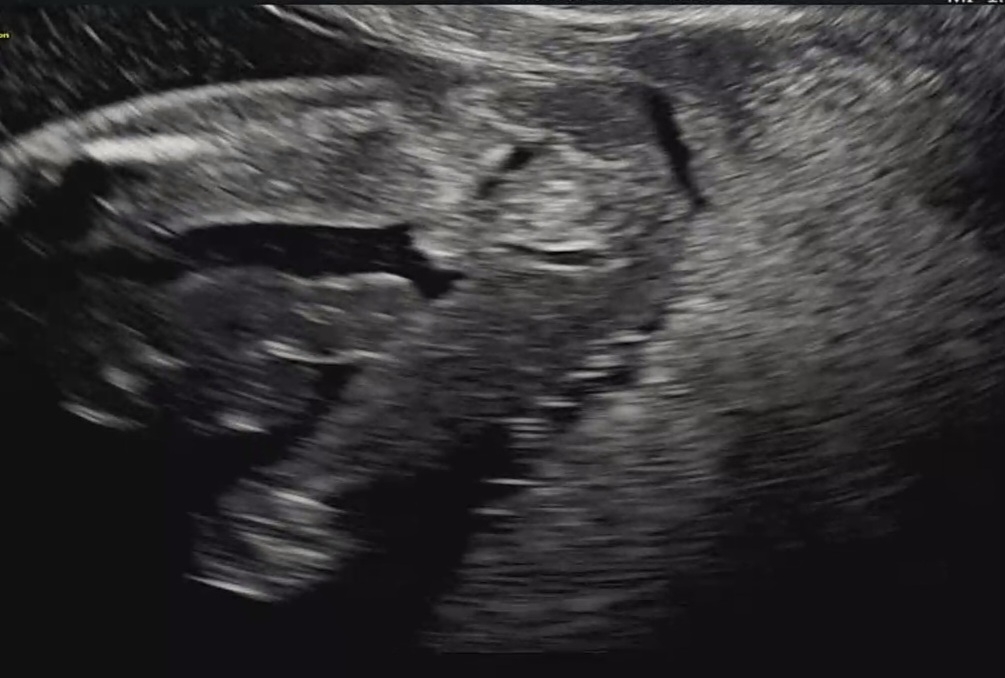

성별봐주세요🥲 16주에요

입체초음파보 얼굴을 양팔로 야무지게 가려주시고, 복부초음파에서 다리꼬기로 안보여주셔서ㅠ 애미 굴욕의 질초음파까지 시켰음서...🥲 의사선생님은 아들이기에는 작은데 또 딸이기에는 음....하시며 요런경우 반전이 많아서 다음 초음파때 보자고 하시는데ㅜ ㅜ 너무 궁금해요!!!!